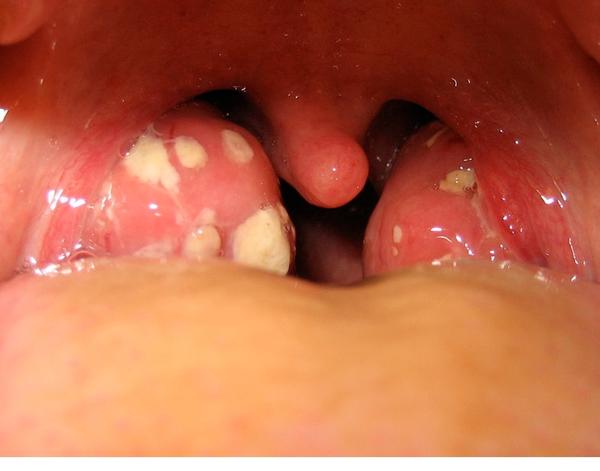

Ahojte vysypali sa mi takto hrdlo ledva prehltam a som stoho nervozny ,teplota ani nic ine mi neni ,dakujem co mi pomoze

@kondrs hnisava angina

@tetapetra toto je hnisava angína, on má len afty

@minenkak začiatok môže vyzerať aj tak, som presne ten typ, ktorý máva len hnisavé angíny

@tetapetra tak uz ma hrdlo zacalo bolet 4 dni dozadu a zrazu toto ,ale replota nic ani kasel. Ani nevim co ,no mozno angina moznonlen tie afty alebonco to je

@kondrs máš afty ,kup tantum verde sprej alebo kloktaj slanú vodu a bude horúčka tak hnisava angína a Bkomplex som zabudla

@kondrs kúp glimbax, ak si v takom štádiu,tam by som radšej šla k lekárovi kvôli ATB

@kondrs je aktualne velmi rozsireny streptokok s atypickym priebehom. Zasla by som na vyter. Pre istotu. Je to mrcha